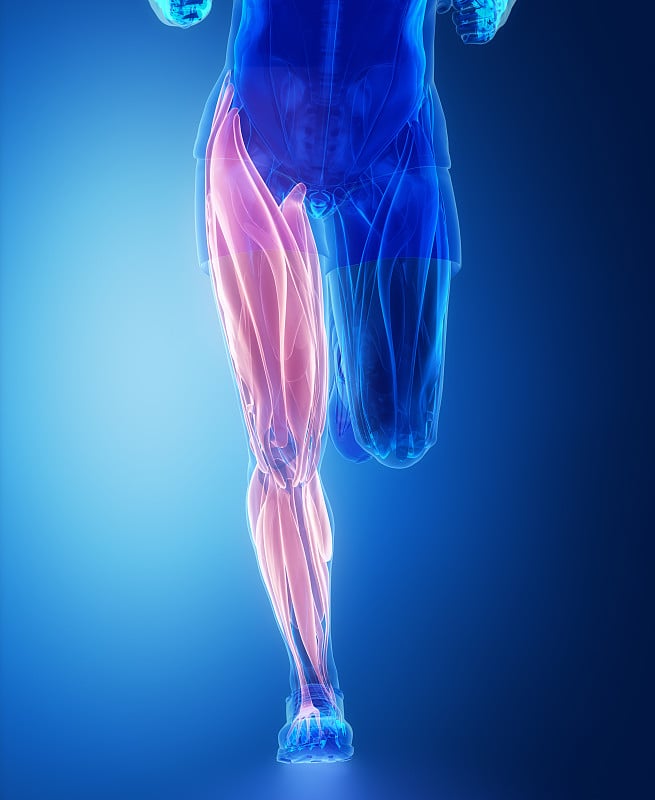

肌肉系统解剖学详情

肌系统解剖学前视图详情

肌系统解剖学前视图详情

肌肉系统解剖学详情

肌肉系统解剖学详情

肌肉系统解剖学详情

肌肉系统解剖学详情

肌肉系统解剖学详情